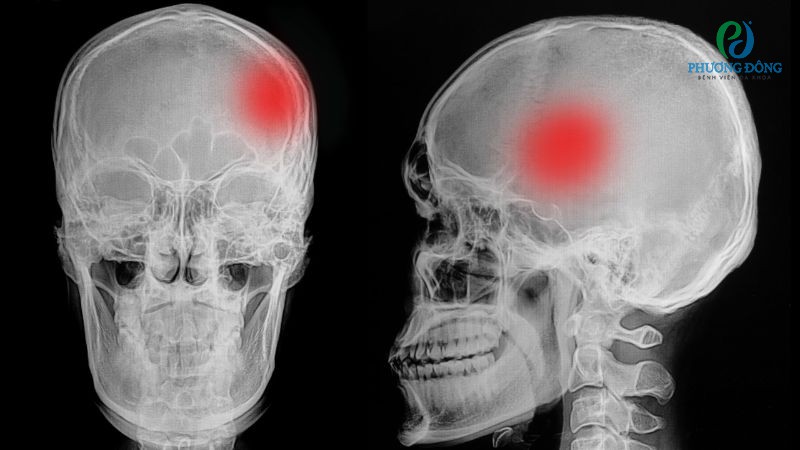

Xương sọ đóng vai trò sống còn trong việc bảo vệ hệ thần kinh trung ương, góp phần tạo hình dạng đặc trưng cho khuôn mặt. Tuy nhiên mọi bệnh lý, tổn thương từ bên trong hay bên ngoài đều có thể ảnh hưởng trực tiếp đến chức năng của loại xương này, đe dọa trực tiếp đến sức khỏe cũng như tính mạng con người.

Xương sọ tuy có cấu trúc chắc chắn cũng khả năng bảo vệ não bộ vượt trội, nhưng vẫn có thể chịu ảnh hưởng bởi các rối loạn và tổn thương khác nhau. Tình trạng thường gặp nhất có thể kể đến tình trạng vỡ, tiêu, viêm hoặc dính khớp sọ, tất cả đều cần được can thiệp sớm nhằm hạn chế biến chứng nguy hiểm.

Vỡ xương sọ

Vỡ là tình trạng xương hộp sọ bị gãy do chấn thương vùng đầu, thường gặp khi nạn nhân vấp ngã, va đập mạnh với vật cứng. Tùy theo mức độ, vị trí sẽ có những dạng vỡ khác nhau như kín, hở hoặc lún.

Vỡ xương sọ là một trong những dạng chấn thương nghiêm trọng

Khi hộp sọ bị vỡ, người bệnh thường gặp các cơn đau đầu dữ dội, buồn nôn, nôn, co giật, mất ý thức, rò rỉ dịch, chảy máu ở mũi hoặc tai. Trường hợp nặng hơn người bệnh bị xuất huyết, tổn thương não đe dọa đến tính mạng.